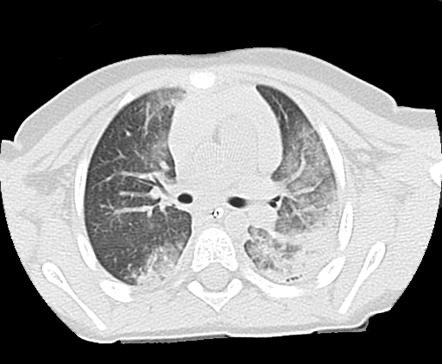

Ağciyər əzilməsi

- Tərifi. Ağciyərin parenxmasına qansızmalardır, küt travmalarda və yelkən döş qəfəsində çox rast gəlinir.

- Təngnəfəslik, sianoz, auskultasiyada xırıltılar şübhə yaradır, KT və ya rentgen diaqnozu dəqiqləşdirir.

- Müalicəsi. Bronxial tualet, ağır vəziyyətlərdə intubasiya və mexaniki ventilyasiya.